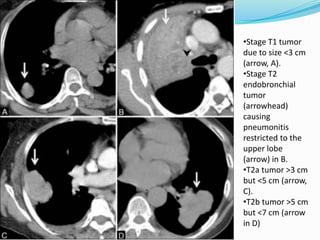

•Stage T1 tumor dueto size <3 cm (arrow, A). •Stage T2 endobronchial tumor (arrowhead) causing pneumonitis restricted to the upper lobe (arrow) in B. •T2a tumor >3 cm but <5 cm (arrow, C). •T2b tumor >5 cm but <7 cm (arrow in D)